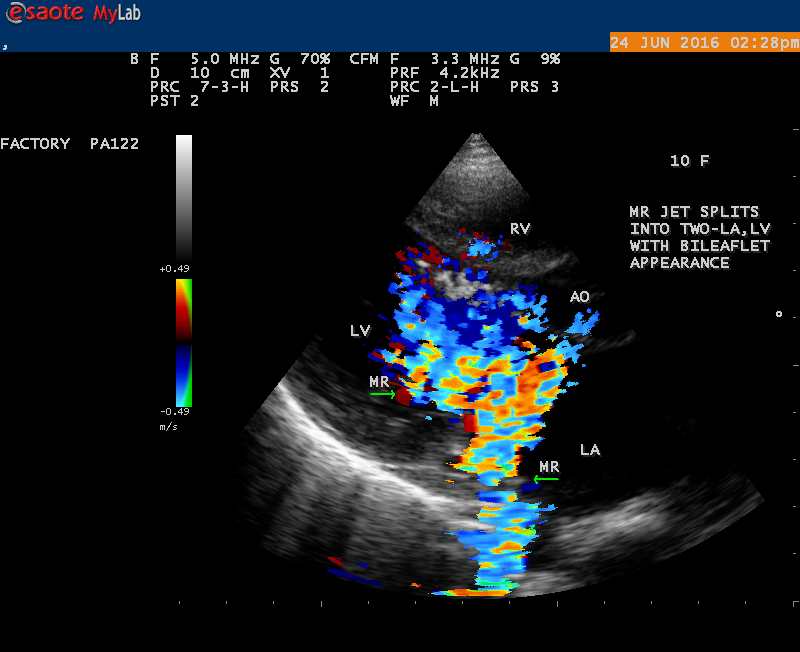

A 10 year female child was referred for echocardiographic evaluation with an apical systolic murmur. The child was having recurrent episodes of rheumatic fever (febrile illness with joint pains) at the age of 5-6 years and taken some treatment from the local medical practitioner, but she was not taken penicillin prophylaxis earlier. The child was remained afebrile for long period and no precipitating factors of infective endocarditis such as dental or genitourinary procedures in the past. General examination revealed normal growth and development, no cyanosis and clubbing and peripheral signs of infective endocarditis such s Osler’s nodes, Janeway lesions, Roths spots and splinter haemorrhages are not present and they are relatively rare in children. Physical examination revealed a grade 3/6 , blowing, high pitched, holosystolic murmur with a constant intensity and duration on dynamic auscultation and loudest at the apex with a radiation to left axilla and transmitted to the left infrascapular area and vertebral coloumn and it is due to the flow generating the murmur is directed posterolaterally within the left atrial cavity, suggesting the murmur of mitral regurgitation due to the rupture of chordae tendineae of anterior mitral leaflet. Blood culture revealed normal. Blood chemistry revealed the positive serum ASO titer, suggesting a recent streptococcal infection and other parameters are normal. X- ray chest reveled moderate cardiomegaly and ECG revealed a left ventricular volume overload pattern of eccentric hypertrophy due to LV dilatation as a result of severe mitral regurgitation and a normal rhythm. Transthoracic echocardiography revealed a giant vegetation ‘popcorn’ like in Figures 1,3 and 4 and ‘cucumber’ like in Figure 2, mainly attached to base and apical portion of anterior mitral leaflet as shown in Figure 31 and manifested in various size and shapes as shown in Figures 1 to 33. A flail anterior leaflet with a disorganized mitral regurgitation jet as shown in Figure 16 and 21 and the posterior leaflet is embedded with vegetation and resulting in ‘kissing forms’ as shown in Figures 13, 14 and 15 in echocardiography imaging. Tricuspid valve is also thickened and calcified as shown in Figure 2 in addition to thickened and calcified mitral leaflets, suggesting an underlying rheumatic etiology predisposing to the formation of vegetation. The child was given 1.2 million units of intramuscular benzathine penicillin injection as a therapeutic and initial prophylaxis dose for rheumatic fever and advised every 3 weeks for life long. Small doses of digoxin and diuretics are also prescribed and advised early surgery (mitral valve replacement) Transthoracic 2D images are as in Figures 1 to 33 are given below

The most common and direct evidence of infective endocarditis is the vegetation and it begins as a microscopic focus of infection and gradually grows into a conspicuous mass. It is typically an irregularly shaped, highly mobile, echogenic mass attached to the free edge of a valve leaflet ( most commonly at the coaptation line) and tends to develop on the ‘upstream’ side of the valve leaflets ( ie, the ventricular side of aortic valve and the atrial side of mitral and tricuspid valves. They may be seesile or pedunculated, but usually has an oscillating or fluttering motion, a typical feature of most vegetations. Vegetation move with the leaflet in a more chaotic (‘oscillating’) manner and it may prolapse through the valve into the LV (left ventricle) as it opens as shown in Figures 3, 4 and 16 and into LA (left atrium) as it closing (Figure 5 and 6) . The mass of vegetation is typically homogeneous with echogenicity similar to that of the myocardium. The infectious process often alter the valvular structure and function. Extensive involvement of the leaflet may result in chordal rupture, leading to severe regurgitation as shown in Figure 21 . Direct and typical signs of RMCT (ruptured mitral chordate tendineae) were chain-flail or whiplash-like changes and had an incidence of 86.7%, causing severe regurgitation and mitral chordal rupture is the leading cause of flail mitral leaflet[30]. A large vegetation may obstruct the valve orifice as shown in Figure 1 and 2 , sometimes termed as “obstructive-type bacterial endocarditis” and producing a functional valve stenosis ( Ping-Pong mitral stenosis [31]) similar to left atrial myxoma as shown in Figure 29.

The shape of vegetation varies in this child as ‘popcorn’ like (Figures 1,3 and 4 ), rod-shaped (Figure ), basket shaped (Figure 7 )[33-Figure 13.3], ‘baby in hand’ appearance (Figure 18), ‘cucumber shaped (Figure 2 ) and a ‘bunch of plantain’appearance (Figure 33 ), ring shaped (Figure 19 }, bileaflet structure (Figure 9 )with bileaflet MR jet as shown in Figure 10 . and kissing forms (Figure 13 - parasternal long axis view, Figure 14 - apical four chamber view and Figure 15 - short axis view)

The anatomic disruption of a portion of the mitral valve apparatus dueto the underlying rheumatic valvulitis with predisposing infective endocarditis which form a vegetation , resulting an eccentric regurgitation jet with orientation opposite in direction of the leaflet having the anatomic defect such as ‘flail’. In the presence of ‘flail leaflet’, the mitral regurgitant spectral signal may have an atypical appearance and the flail portion oscillate in the spectral signal of regurgitant flow stream to produce a ‘tiger stripe’ appearance as shown in Figure 27. associated with ‘whistling’ sound on auscultation[33-Figure 11.85]. The mitral regurgitation (flail MR) jet is chaotic as shown in Figure 26, highly eccentric (Figure 22) and disorganized with one component behind the anterior mitral leaflet and the second component directed towards posterior immediately as in Figure 21 [33- Figure 11.79].

The severity of eccentric MR is underestimated because of coanda effect. If the regurgitant jet area fills < 20> 40% indicate severe regurgitation. The vena contracta ( the neck or narrowest portion of the jet), typically imaged perpendicular to the commissural line in parasternal long axis and apical four chamber views is well defined in both central and eccentric jets, but not in chaotic, disorganized jets due to flail leaflets. Its width < 3> 7 mm defines severe MR and a mean value of > 8mm indicates severe functional MR. The flow convergence method based on PISA (proximal isovelocity surface area) may not applicant for eccentric and multiple jets or complex and elliptical regurgitant orifices to assess the severity of mitral regurgitation.. The adaptation of LV to the increased volume overload is reflected by LV dimensions and ejection fraction.. In chronic compensated phase, the forward stoke volume is maintained through an increase in LV ejection fraction >65% and the patient could be asymptomatic. In chronic decompensated phase of MR, the forward stroke volume decreases and the LA pressure increase significantly. The patient may be still asymptomatic and the LV ejection fraction may be in the low normal range despite the presence of significant muscle dysfunction. The contractile function decreases silently and become irreversible. In the current guidelines, surgery is recommended in asymptomatic patients with severe organic MR when the LV ejection fraction is ≤ 60%. However, in acute stage, the LV ejection fraction increases in response to the increased preload. The end-systolic diameter is less preload dependent than the ejection fraction and it may be more appropriate to monitor the global LV function. The end-systolic diameter > 45 mm also indicate the need for mitral valve surgery [43]. In this child, the LVESD (end-systolic diameter) is 30.7 mm and the ejection fraction (EF) is 66% as shown in Figure 19. New parameters are currently available for a better assessment of LV function. A systolic tissue Doppler velocity measured at the lateral annulus <10>40-50mm) may predict the onset of atrial fibrillation and poor prognosis in patients with organic MR[48]. The excess regurgitant blood entering in the LA may induce acutely or chronically a progressive rise in pulmonary pressure and the presence of TR (tricuspid regurgitation) as shown in Figures 26 and 28 permits the estimate of systolic pulmonary arterial pressure and mitral valve surgery is recommended when it is > 50 mmHg at rest and LA reverse remodeling may occur after surgery. The severe TR may cause a decrease in hepatic vein systolic velocity and systolic flow reversal may occur as shown in Figure 32 and its sensitivity is 80% [49]. The TR (tricuspid regurgitation) jet velocity in this child is 4.03 m/s as shown in Figure 28 which corresponds to a systolic pulmonary artery pressure of 65 mmHg.